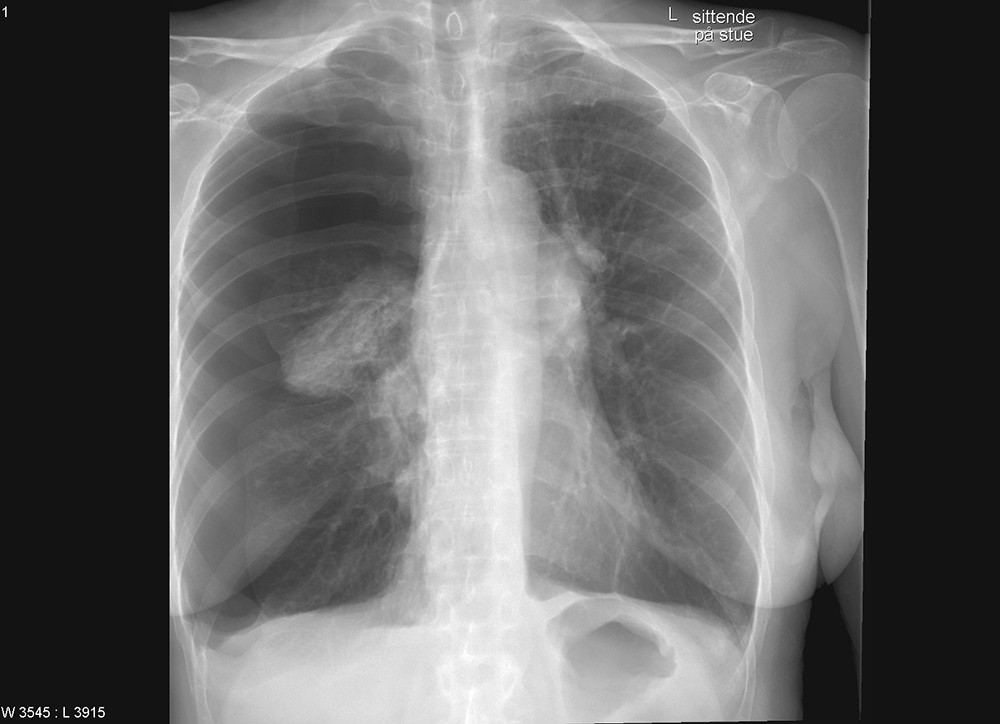

En kvinne i 60-årene var innlagt med svelgevansker og ernæringsproblemer. Hun var fra tidligere diagnostisert med supraglottisk plateepitelcancer og behandlet med utvidet strålefelt mot halsen og med cytostatika. Ved denne innleggelsen fikk hun lagt ned en tynn nasogastrisk sonde. Sonden hadde ytre diameter 1,95 mm og en stålmandreng. Den lot seg tilsynelatende føre ned ukomplisert. Ved instillasjon av 10 ml luft hørtes ikke bobler som normalt over magesekken. Røntgen av nedre thorax og øvre abdomen viste at sonden hadde fulgt bronkialtreet langt ut i høyre lunge (bilde til venstre). Sonden ble fjernet, men kort tid etter fikk kvinnen store pusteproblemer og stansalarmen måtte aktiveres. Røntgen thorax viste en stor høyresidig pneumothorax (bilde til høyre). Den ble vellykket behandlet med kirurgisk anlagt pleuradren.

Pasienter med gjennomgått cancer og strålebehandling i øre-nese-hals-området har ofte store ernærings- og svelgevansker som gjør det nødvendig å legge ned en nasogastrisk sonde. Samtidig er ofte anatomiske forhold endret og vanlige reflekser svekket, slik at man må være ekstra varsom ved nedlegging av sonden. Det finnes imidlertid også flere beskrivelser av pasienter uten strålebehandlet kreftsykdom, noen med trakeostomitube og orale tuber med oppblåst mansjett, som har fått lagt ned tynn ernæringssonde ut gjennom pleura uten symptomer (1), for så å få en alvorlig pneumothorax i det ernæringssonden dras tilbake. Dette skjedde også hos vår pasient. Pleuradrenberedskap anbefales derfor før ernæringssonden trekkes ut (1).